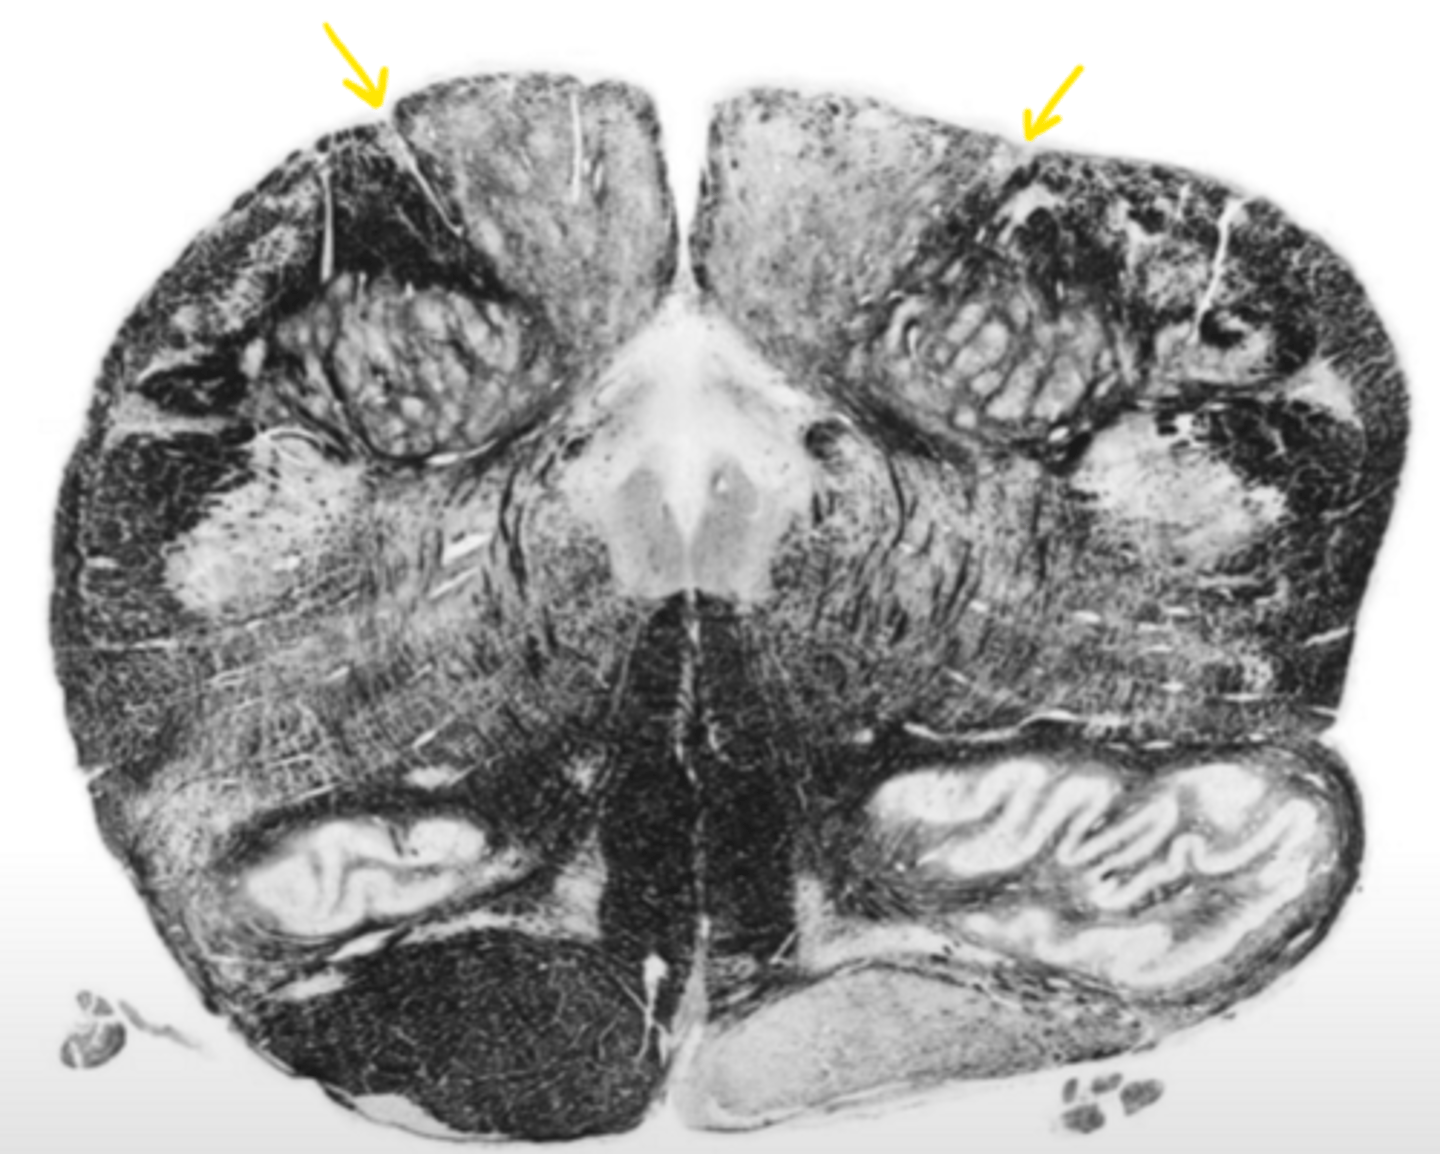

open medulla

ID the brainstem level